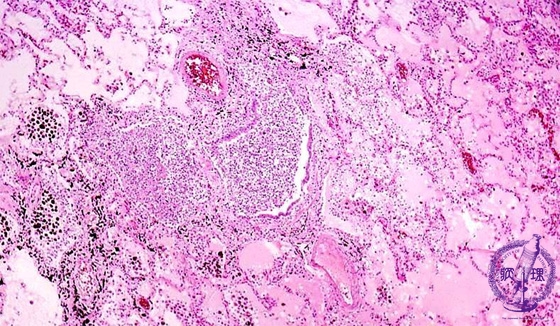

- ★(7)Bacterial pneumonia (bronchopneumonia)

Microscopic view (HE stain, low power view): The bronchiole is filled with purulent debris and surrounded by edema and an inflammatory infiltrate. Bronchial structure is obscured due to destruction of bronchial alveoli (dotted line).